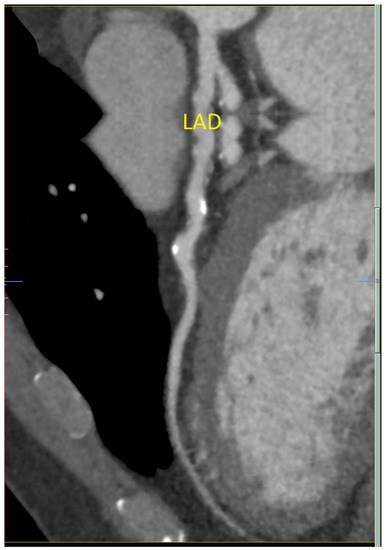

A 58-year-old man presented to medical attention with atypical chest tightness with exertion. He has a history of hypertension, hyperlipidemia, and orthostatic dizziness/pre-syncope. He has no history of diabetes and is a non-smoker. He underwent investigations including an electrocardiogram (ECG) and an exercise stress test, which were both normal. Echocardiogram was unremarkable as well, revealing mildly concentrically increased left ventricular wall thickness and mild biatrial enlargement. Cardiac computed tomography demonstrated diffuse non-obstructive coronary artery disease (CAD). The right coronary artery (RCA) was shown to have a cylindrical aneurysmal dilatation over 38 mm with associated plaque and the proximal left anterior descending (LAD) artery had an ulcerated noncalcified plaque (25–49%) (Figure 1). He has no specific family history for premature CAD, arrhythmia or sudden cardiac death.

Figure 1.

Cardiac computed tomography showing diffuse ectasia of the left anterior descending (LAD) artery.